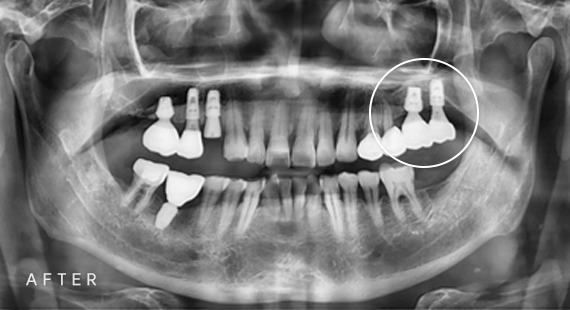

임플란트